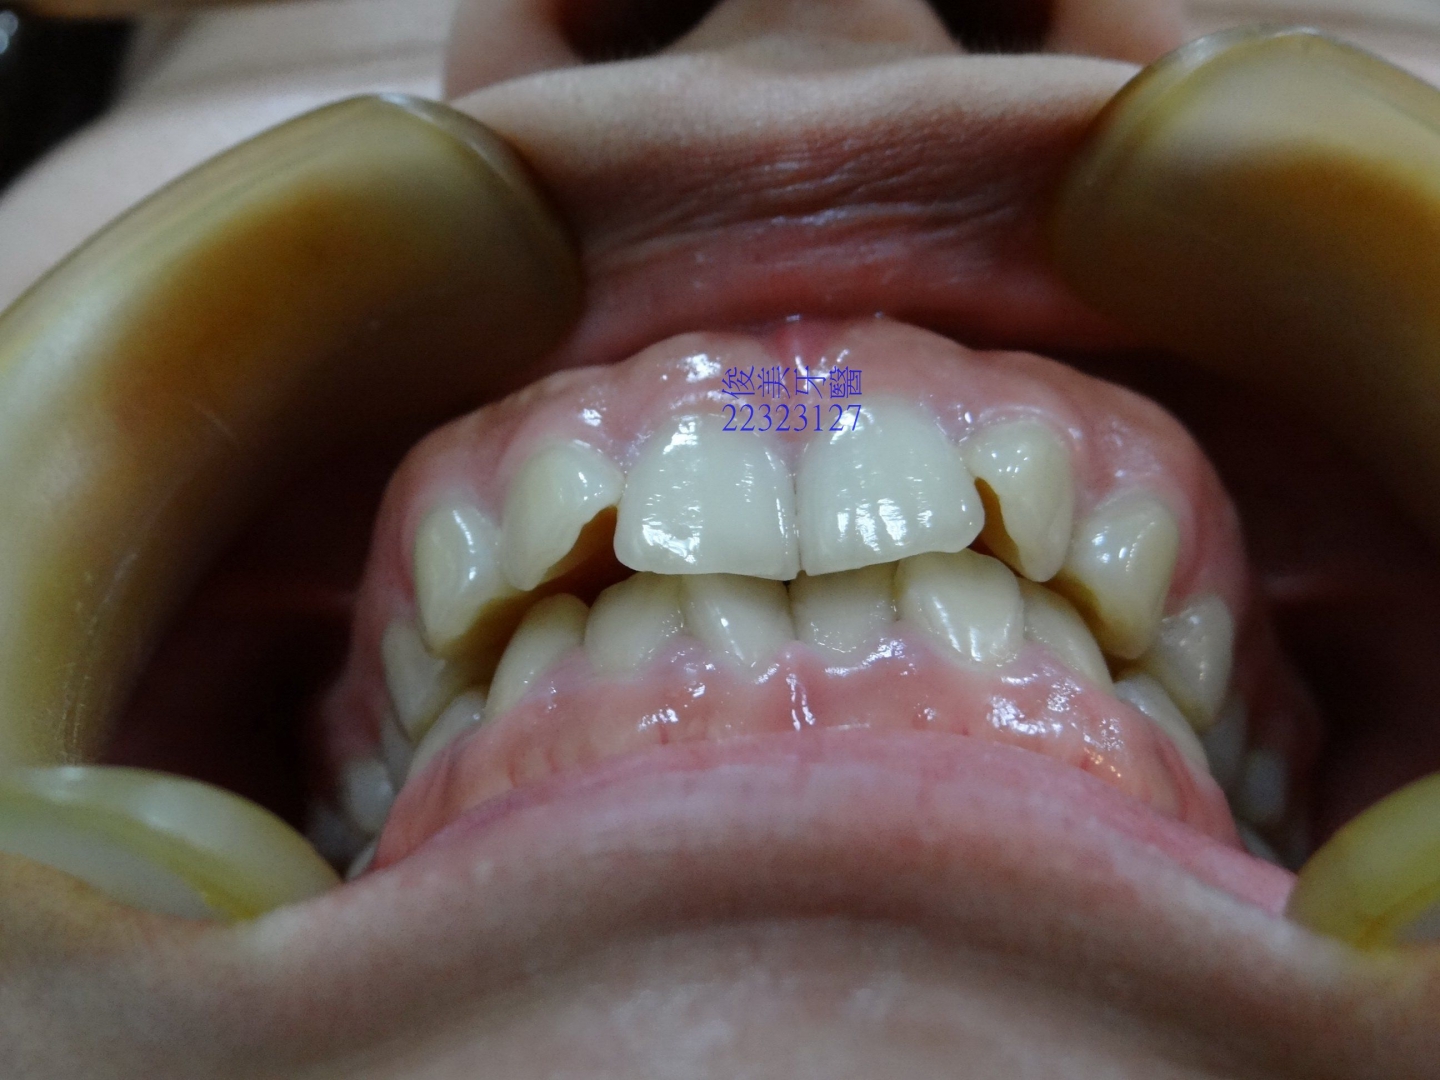

![]() 患者於門診中表示,牙齒很擁擠,想要改善;經醫師門診後,建議患者進行矯正治療即可改善。 ![]() 牙齒重疊... ![]() 有深咬現象... ![]() 上顎狀況... ![]() 下顎狀況... ![]() 左側咬合,牙齒往舌側傾斜...... . ![]() 右側咬合,牙齒往舌側傾斜...... ![]() 治療中....擁擠和深咬已改善.... ![]() 牙齒往後移.....將牙齒齒軸回正一點。 ![]() 治療結束,拆除矯正器了............. ![]() 患者好開心......牙齒整齊後,笑容更可愛了。 ![]() 也沒有暴牙的狀況。 ![]() 上顎牙弓狀況。 ![]() 下顎牙弓狀況。 ![]() 右側咬合狀況。 ![]() 左側咬合狀況。 ![]() 已拆除超過5年,依舊配戴維持器,保持最佳狀態。 |